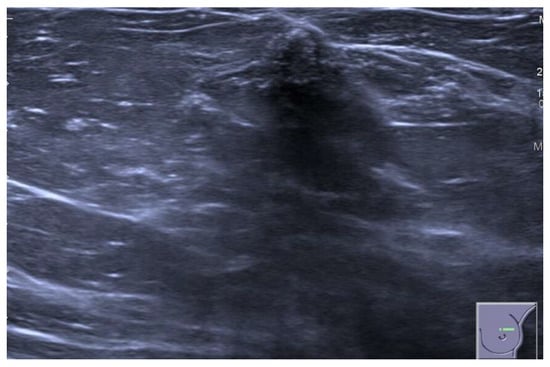

4.2. Ultrasound